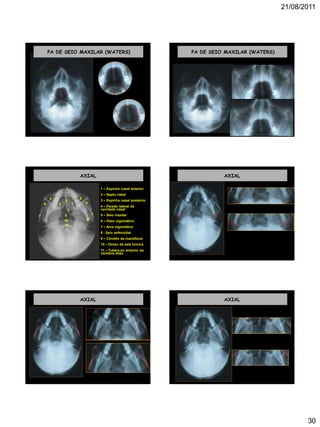

PA DE SEIO MAXILAR (WATERS)

1 – Seio maxilar

2 – Órbita

3 – Seio esfenoidal

4 – Osso nasal

5 – Septo nasal ósseo

6 – Espinha nasal

posterior

7 – Arco zigomático

1 1

2 2

33

4 4

5

6

7

PA DE SEIO MAXILAR (WATERS) PA DE SEIO MAXILAR (WATERS)

AXIAL

1 – Espinha nasal anterior

2 – Septo nasal

3 – Espinha nasal posterior

4 – Parede lateral da

cavidade nasal

5 – Seio maxilar

6 – Osso zigomático

8 - Seio esfenoidal

9 – Côndilo da mandíbula

10 – Dorso da sela túrcica

11 – Tubérculo anterior da

vértebra atlas

1

2

3

5 5

6 6

78

910

11

AXIAL AXIAL